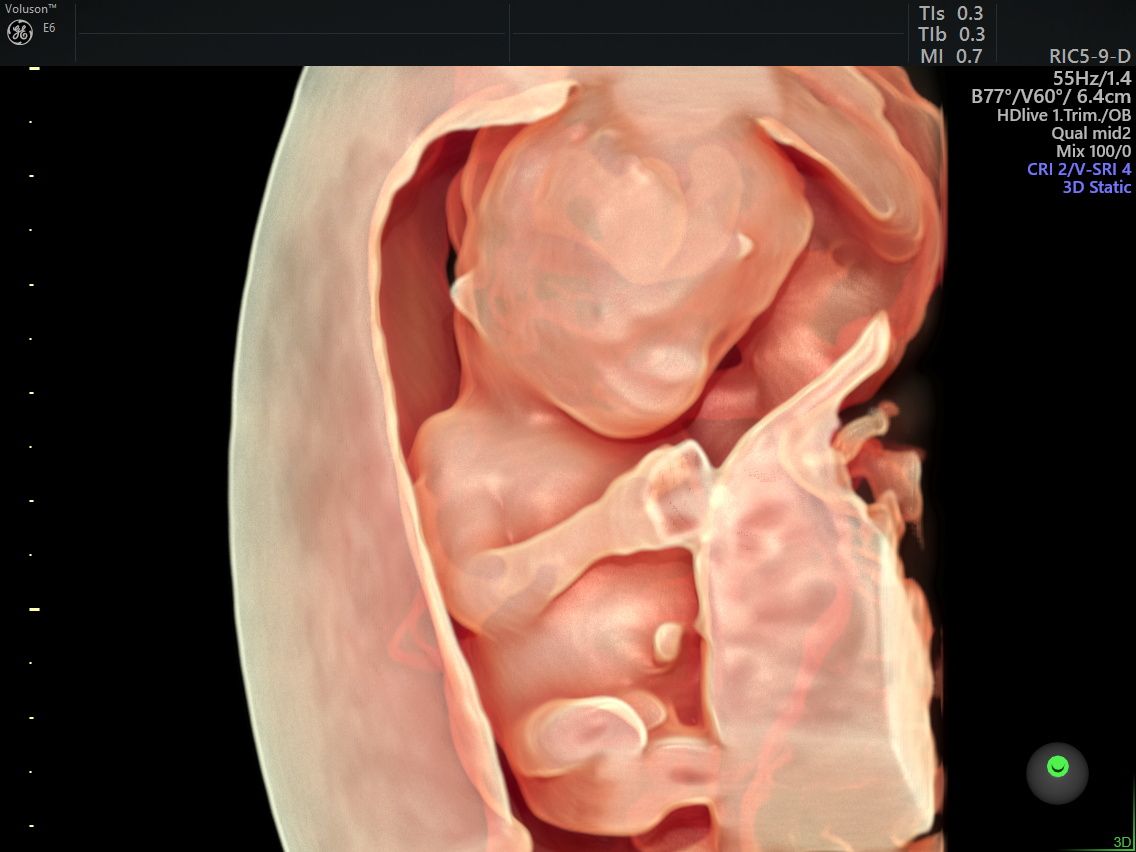

Realizo estudios con tecnología avanzada para detectar posibles complicaciones durante el embarazo. Entre ellos se incluyen ultrasonidos de tamizaje en el primer trimestre, ultrasonidos estructurales, seguimiento de embarazos gemelares y pruebas genéticas como ADN fetal, biopsia de vellosidades coriales y amniocentesis, que ayudan a evaluar la salud del bebé y del embarazo.

Fotos y videos